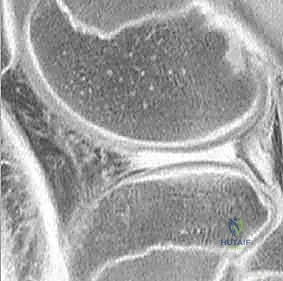

- التصوير بالرنين المغناطيسي (MRI): هو المعيار الذهبي (Gold Standard) لتشخيص تمزقات الغضروف الهلالي. يوفر صوراً ثلاثية الأبعاد وعالية الدقة للأنسجة الرخوة. من خلال الرنين، يستطيع الدكتور هطيف تحديد نوع التمزق، حجمه، موقعه (في أي منطقة دموية)، وما إذا كانت هناك إصابات مصاحبة (مثل تمزق الرباط الصليبي الأمامي ACL).